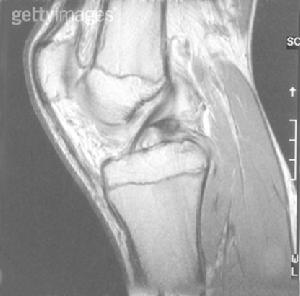

外傷史和明顯的膝部體徵結合X線MRI檢查一般診斷不難少數患者因急性損傷疼痛,股四頭肌保護性痙攣,前抽屜試驗陰性,需在麻醉下進一步檢查方法詳見後十字韌帶損傷。

膝關節鏡檢查沖淨積血,可見ACL斷裂端出血或小血塊凝集。滑膜下韌帶損傷在關節鏡下貌似正常,但其長度及張力異常可提示本損傷的可能性。膝關節X線檢查,可顯示脛骨髁間隆凸骨折,內外應力檢查時可見一側關節間隙加寬。

3、MRI急性期MRI檢查確診率可達5%以上慢性期由於體徵明確,MRI檢查並非必要。